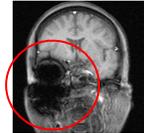

| 非常に強力な磁石を使用しているため、原則として金属類を検査室に持ち込むことはできません。体内に医療機器(ペースメーカー、除細動器、神経刺激装置、人工内耳等)を埋め込んでいる方は検査を受けられません。しかし最近は,ペースメーカを始めとする体内金属でもMR対応の医療機器が発売され挿入されている患者様が多数おられます.これらはある一定の条件下でMR検査を認められているものなので,事前のチェックなしに検査はできません.他にも脳動脈瘤クリップ、ステント等、体内に金属の入っている方も同様ですので、事前に医療機関にご確認ください。 右の頭部画像の赤丸で囲った部分は、入れ歯の金属の影響で必要な信号を得られなかった部分です。このようにMR検査では金属に対して注意が必要です。 |

![]() |